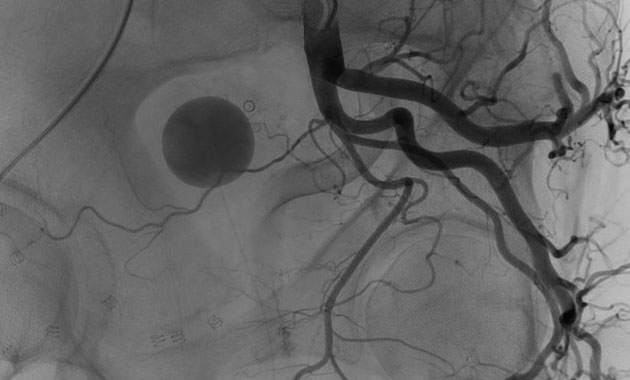

The treatment is done by an interventional radiologist using X-rays and advanced imaging to block the arteries supplying the prostate, which leads to a decrease in size and reduced symptoms. Dr. Kunal Arora uses his expertise to deliver accurate, safe, and efficient Prostate Artery Embolization treatment in Mumbai for effective relief.

Dr. Kunal Arora can prescribe imaging tests like a CT scan or angiogram. Imaging tests accurately map the prostate arteries and guide precise planning of treatment to achieve effective outcomes.

The procedure is performed under local anaesthetic, in which a catheter is inserted through the groin to the arteries of the prostate gland. Microspheres or embolic coils are released to reduce the blood flow, and thus, safely shrink the prostate.